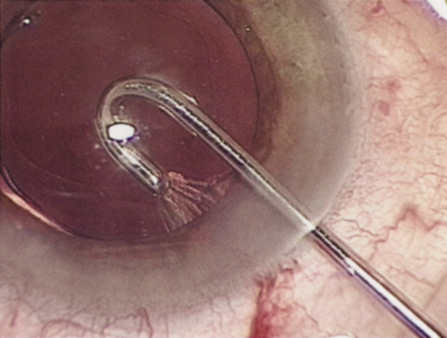

HYDRODISSECTION Hydrodissection can be performed after the surgeon has successfully completed capsulorrhexis.97 If the capsulorrhexis is not intact, fluid forced around the interior of the capsule may cause the bag to splay open. With capsulorrhexis, hydrodissection is a safe and extremely useful maneuver. Hydrodissection can be thought of as two maneuvers: hydrodelineation and cortical cleaving hydrodissection. By placing a 27-gauge cannula on a syringe filled with balanced saline solution (BSS), the surgeon can direct fluid beneath the residual anterior capsular rim to create a cleavage plane. Depending on the direction the fluid wave takes, different lamellae of the cataract will be separated. Hydrodelineation is the term used when the cleavage plane separates the adult nucleus from the fetal nucleus or the adult nucleus from the more peripheral epinucleus. Hydrodelineation often results in the characteristic golden ring sign (Fig. 11). Cortical cleavage occurs when the cortex is separated from the capsular bag (Fig. 12). Finding the cortical cleavage plane may be facilitated by gently lifting the capsular margin away from the cortex with the BSS cannula before injecting. Several small bursts of fluid allow the surgeon to monitor progress of the fluid wave. When dealing with a soft nucleus, the authors strive to perform true cortical cleaving hydrodissection. For a hard nucleus, hydrodelineation allows manipulation of less of the nuclear bulk, although the remaining epinuclear shell must be addressed in an additional step. Hydrodelineation is particularly useful if the nucleus is not freely mobile after cortical cleaving hydrodissection.